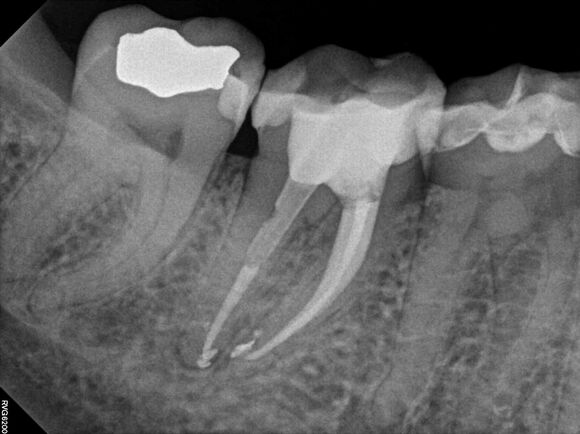

Beispiel 1: Vorher

Schwierige Krümmungen und sehr grazile Wurzeln.

Beispiel 1: Nachher

Die perfekte Wurzelfüllung!